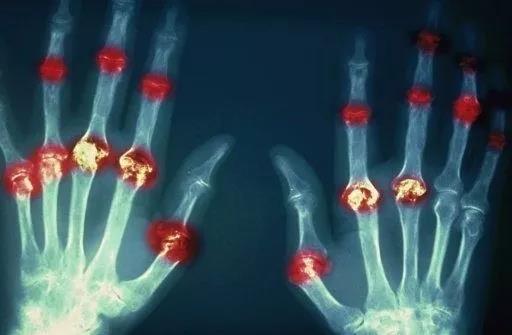

? 類風(fēng)濕關(guān)節(jié)炎

類風(fēng)濕關(guān)節(jié)炎是一種高度致殘的自身免疫性疾病,發(fā)病十年的患者中至少有50%的人失去勞動(dòng)能力。

類風(fēng)濕關(guān)節(jié)炎©Health Same of Flickr

1977年,Baldwin在用骨髓干細(xì)胞移植治療再生障礙性貧血的過(guò)程中,意外發(fā)現(xiàn)患者的類風(fēng)濕關(guān)節(jié)炎得到緩解。

2004年,歐洲骨髓移植和抗風(fēng)濕病聯(lián)盟對(duì)60例類風(fēng)濕病關(guān)節(jié)炎移植患者進(jìn)行回顧性分析,這些患者的關(guān)節(jié)破壞都達(dá)到不可修復(fù)程度,生活不能自理,通過(guò)干細(xì)胞移植治療后,67%的患者得到明顯緩解。

我國(guó)國(guó)內(nèi)多家醫(yī)院已開(kāi)展了干細(xì)胞治療類風(fēng)濕性關(guān)節(jié)炎的臨床研究。首例自體干細(xì)胞移植治療類風(fēng)濕關(guān)節(jié)炎在北京協(xié)和醫(yī)院完成。經(jīng)過(guò)5個(gè)月隨訪,這些經(jīng)常規(guī)藥物治療失敗且病情發(fā)展迅速的患者,在接受干細(xì)胞移植治療后,癥狀均獲得改善,關(guān)節(jié)腫脹消失,各項(xiàng)檢查指標(biāo)恢復(fù)正常。

解放軍323醫(yī)院2011年的一項(xiàng)臨床研究中,27位患者(對(duì)照組)只使用藥物治療;另外153位患者(細(xì)胞治療組)在藥物治療的基礎(chǔ)上進(jìn)行臍帶間充質(zhì)干細(xì)胞輸注。結(jié)果顯示,治療組DAS28、HAQ 評(píng)分、ACR20較對(duì)照組下降明顯(分值越低,療效越好),Th1/Th2趨于平衡、Treg升高與臨床實(shí)驗(yàn)指標(biāo)及癥狀的緩解直接相關(guān)。